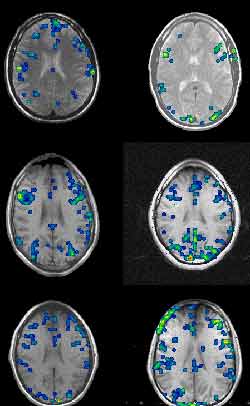

Functional MRI of a 24-year-old woman during a word-generation

task (Source : Dept. of Neurology and Radiology, Münster)

Functional MRIs taken while six different subjects performed

the Stroop text. Note the large variations from one person to another. (Source

: Dr. David C. Osmon)